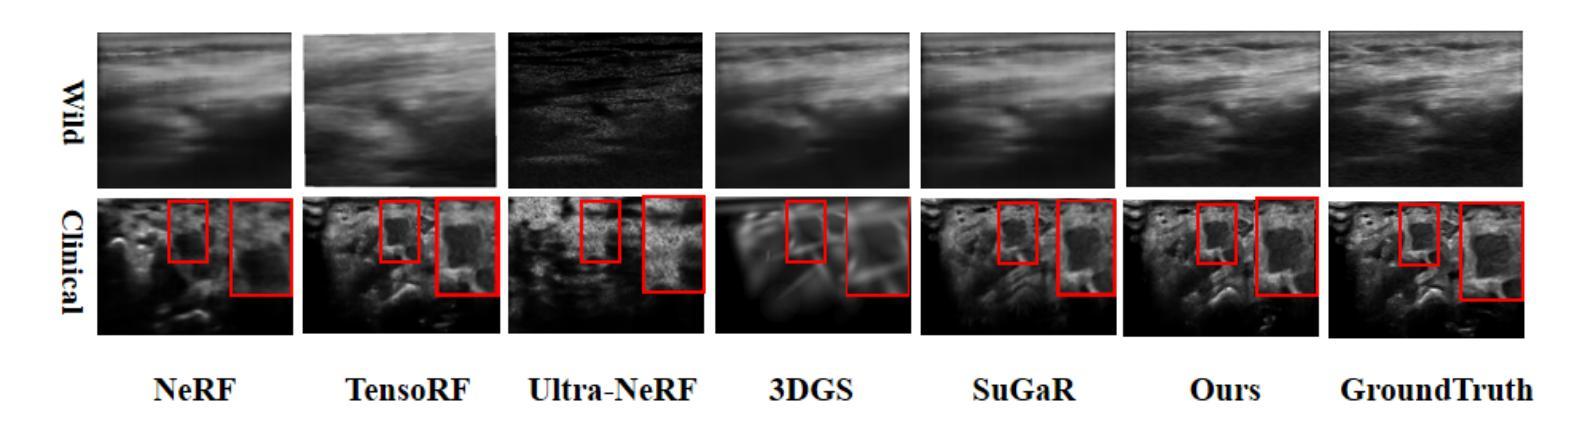

UltraGS: Gaussian Splatting for Ultrasound Novel View Synthesis

Ultrasound imaging is a cornerstone of non-invasive clinical diagnostics, yet its limited field of view complicates novel view synthesis. We propose \textbf{UltraGS}, a Gaussian Splatting framework optimized for ultrasound imaging. First, we introduce a depth-aware Gaussian splatting strategy, where each Gaussian is assigned a learnable field of view, enabling accurate depth prediction and precise structural representation. Second, we design SH-DARS, a lightweight rendering function combining low-order spherical harmonics with ultrasound-specific wave physics, including depth attenuation, reflection, and scattering, to model tissue intensity accurately. Third, we contribute the Clinical Ultrasound Examination Dataset, a benchmark capturing diverse anatomical scans under real-world clinical protocols. Extensive experiments on three datasets demonstrate UltraGS’s superiority, achieving state-of-the-art results in PSNR (up to 29.55), SSIM (up to 0.89), and MSE (as low as 0.002) while enabling real-time synthesis at 64.69 fps. The code and dataset are open-sourced at: https://github.com/Bean-Young/UltraGS.

超声成像作为非侵入性临床诊断的基石,但其有限的视野给新型视图合成带来了困难。我们提出了针对超声成像优化的高斯Splatting框架——UltraGS。首先,我们引入了一种深度感知的高斯Splatting策略,其中每个高斯被分配一个可学习的视野,从而实现准确的深度预测和精确的结构表示。其次,我们设计了SH-DARS,这是一个轻量级的渲染功能,结合了低阶球谐函数和超声特定的波物理,包括深度衰减、反射和散射,以准确模拟组织强度。第三,我们贡献了临床超声检查数据集,这是一个基准测试集,捕获了真实世界临床协议下的多种解剖扫描。在三个数据集上的广泛实验证明了UltraGS的优越性,在PSNR(高达29.55)、SSIM(高达0.89)和MSE(低至0.002)方面达到最新水平的结果,同时以每秒64.69帧的速度实现实时合成。代码和数据集已在https://github.com/Bean-Young/UltraGS开源。

Summary

超声波成像在临床诊断中扮演着重要角色,但其有限的视野给新型视图合成带来挑战。本研究提出一种针对超声波成像的Gaussian Splatting框架——UltraGS。它采用深度感知的高斯喷绘策略,并结合低阶球谐函数与超声波特定波动物理的轻量化渲染功能SH-DARS,实现精准结构表征与强度建模。此外,该研究还公开了符合真实临床协议的多解剖部位扫描数据集,并验证了UltraGS在PSNR、SSIM和MSE指标上的优越性,同时实现实时合成。

Key Takeaways

• UltraGS是一个针对超声波成像的Gaussian Splatting框架。

• 引入深度感知的高斯喷绘策略,使每个高斯具有可学习的视野,提高深度预测和结构化表征的准确性。

• 设计了结合低阶球谐函数与超声波特定波动物理的轻量化渲染功能SH-DARS,以准确模拟组织强度。

• 公开了临床超声波检查数据集,包含多种解剖部位扫描,符合真实临床协议。

• 在三个数据集上的实验验证了UltraGS的优越性,在PSNR、SSIM和MSE指标上达到最新水平。

• UltraGS能够实现实时合成,达到64.69帧每秒。